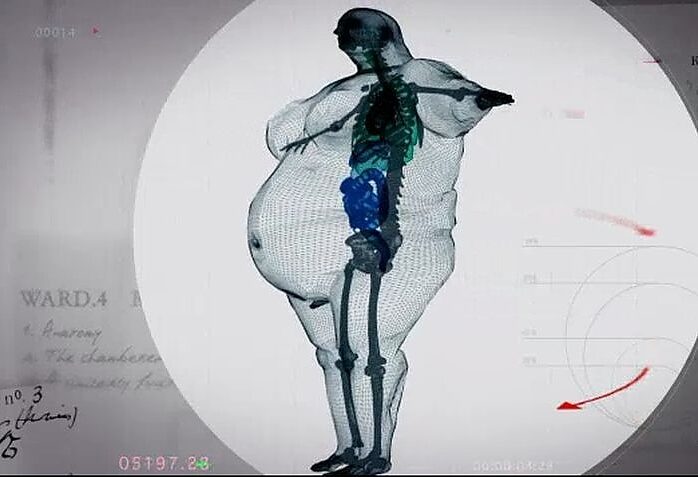

Martin, uzun yıllardır obezite hastasıDoktorlar, Martin eğer kilo vermezse 2 yıl ömrü kaldığını söylüyorlar.Martin’in Xray görüntüleri sosyal medyada büyük ilgi gördü. Çünkü Martin’in her insan gibi normal boyutta bir kemik yapısı vardıBu görüntüler zayıflamamak için kendine bahane bulan diğer kilolu insanları bilgilendirmek için dağıtılıyor.

Martin’in Xray görüntüleri sosyal medyada büyük ilgi gördü. Çünkü Martin’in her insan gibi normal boyutta bir kemik yapısı vardı